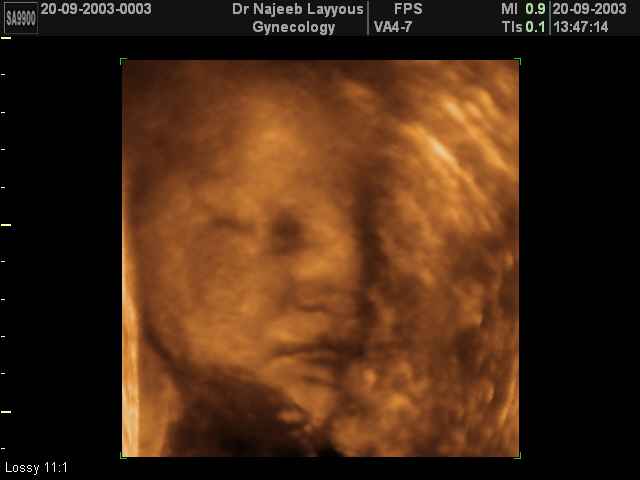

صور لوجه الجنين بجهاز الالتراساوند ثلاثي الأبعاد | الدكتور نجيب ليوس

صور لوجه الجنين بجهاز الموجات فوق صوتية ثلاثي الأبعاد